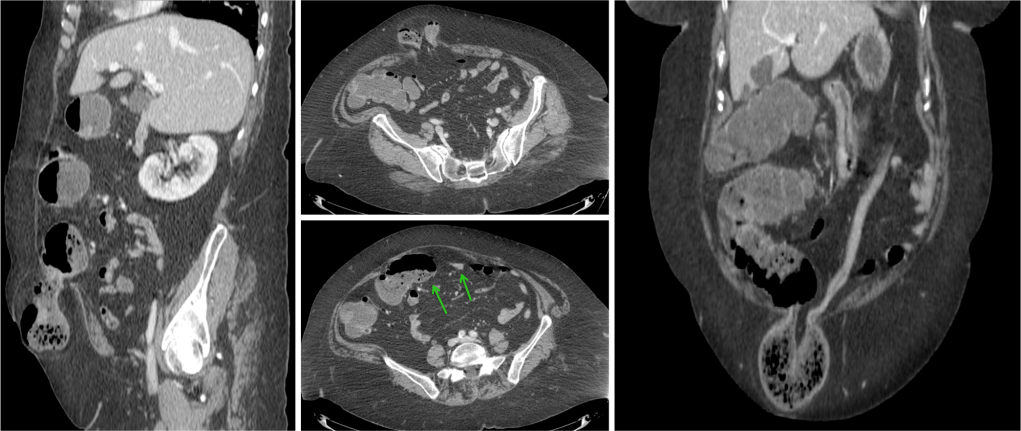

El íleo biliar se define como la obstrucción mecánica causada por la impactación en el lumen intestinal de una litiasis biliar procedente de la vesícula. Es una complicación que ocurre en el 0.3 – 0.5% de todas las colelitiasis.

Aunque su frecuencia global es baja, en pacientes ancianos no lo es tanto, llegando a constituir alrededor del 25% todas las obstruciones intestinales no estranguladas. Al igual que en la coletitiasis, es más frecuente en mujeres.

Su mortalidad varía entre el 8 -30%, llega a ser bastante alta sobre todo en ancianos con patología concomitante.

Placa simple: Triada de Rigler: Obstrucción de asas de delgado + gas en el arbol biliar + litiasis (frec en la FID); estos tres hallazgos constituyen la Triada de Rigler.

Tomografía computarizada: S y E del 93% y 100% respectivamente. Hallazgos: Dilatación por obstrucción de asas de delgado. Aerobilia. Litiasis (2 – 3 cm aprox). Hay que tener cuidado ya que muchas litiasis no están calcificadas y su densidad puede ser similar al contenido del intestino. Pueden ser multiples, por tanto hay que poner atención para que no pasen desapercibidas y evitar las recidivas. Fistulas (normalmente entre vesícula y duodeno). Neumoperitoneo (gas portal o gas mural indican peor pronóstico).

Sindrome de Bouveret: Es un tipo de íleo biliar muy proximal y poco frecuente, donde una litiasis migra a través de una fístula desde la vesícula biliar al duodeno proximal o al píloro gástrico, produciendo ahí una obstrucción.